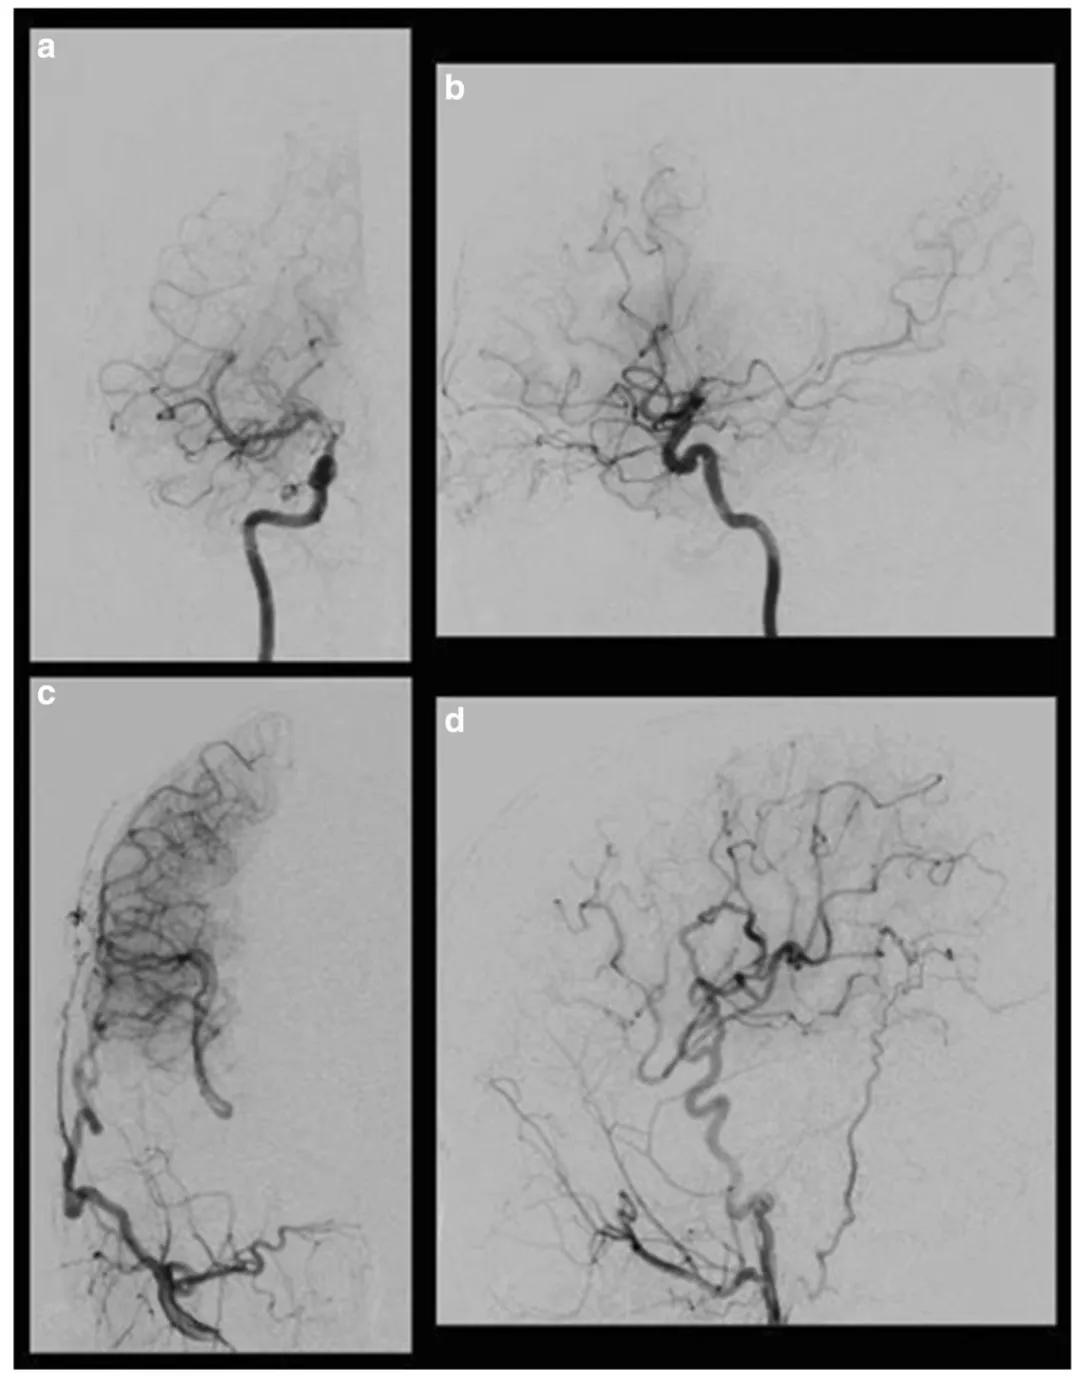

术后7个月复查血管造影显示(图3):新建血管通畅良好,颈外动脉血流经搭桥血管有效灌注至右侧大脑中动脉区域,证实手术不仅缓解症状,更从根本上改善脑组织血流灌注。

图3术后右侧颈动脉血管造影显示:经右侧颈外动脉的搭桥血管向大脑中动脉(MCA)和大脑前动脉(ACA)供血不足区域供血。(a)右侧颈内动脉正位观;(b)右侧颈内动脉侧位观;(c)右侧颈外动脉正位观;(d)右侧颈外动脉侧位观